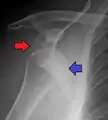

X-ray at left shows anterior dislocation in a young man. X-ray at right shows the same shoulder after reduction and internal rotation, revealing a Bankart lesion and a Hill-Sachs lesion.

In over 95% of shoulder dislocations, the humerus is displaced anteriorly.[7] In most of those, the head of the humerus comes to rest under the coracoid process, referred to as sub-coracoid dislocation. Sub-glenoid, subclavicular, and, very rarely, intrathoracic or retroperitoneal dislocations may also occur.[8]

A Hill–Sachs lesion is an impaction of the head of the humerus left by the glenoid rim during dislocation.[6] Hill-Sachs deformities occur in 35–40% of anterior dislocations. They can be seen on a front-facing X-ray when the arm is in internal rotation.[9] Bankart lesions are disruptions of the glenoid labrum with or without an avulsion of bone fragment.